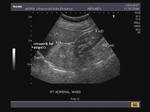

Adrenal mass

Mass in suprarenal region

These sonographic images reveal a space occupying lesion above the right kidney in the region of the right adrenal gland . The mass is large, echogenic and poorly defined and pushes the kidney downwards. It shows an inhomogenous appearance, but no calcification is present. The retroperitoneal fat stripe is displaced anteriorly by the mass proving that it is of adrenal and not hepatic origin (see the arrowheads in third image). These ultrasound images of the right adrenal mass suggest likelihood of malignancy. Differential diagnosis includes: 1) adrenal adenoma 2) pheochromocytoma 3) metastasis. Large masses of the type seen here are highly suggestive of malignancy of the adrenal gland. However, the color doppler image shows scanty vascularity of the mass.

Ultrasound images courtesy of Dr. Vikas Arora, Ferozepur, India, using a Nemio 30 Ultrasound and color doppler machine.